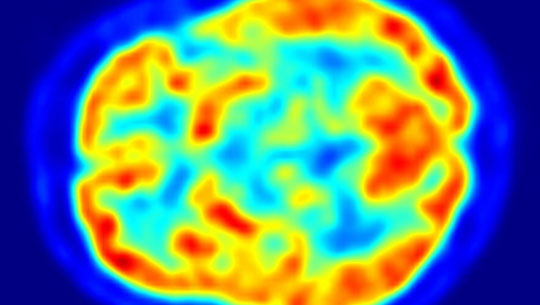

«Desarrollamos un nuevo método para rastrear las etapas iniciales de agregación de alfa-sinucleína. Utilizamos microscopía de súper resolución y un análisis avanzado», afirmó Uri Ashery, coautor del estudio y director de la Escuela de Neurociencia Sagol de la Universidad de Tel Aviv (TAU).

El científico explicó que, junto a sus colaboradores en la Universidad de Cambridge que desarrollaron un modelo de ratón especial para la enfermedad de Parkinson, pudieron detectar diferentes etapas de la agregación de esta proteína. “Correlacionamos la agregación con el deterioro de la pérdida de actividad neuronal y los déficits en el comportamiento de los ratones. Este es un avance significativo en el mundo de la investigación de Parkinson”. añadió.